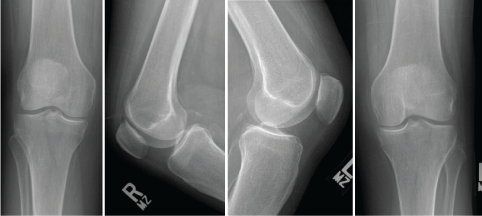

SS is a 60-year-old Female, with no significant past medical history, who presented to our facility with a long-standing history of bilateral knee pain (R > L), however six months prior to presentation she had an acute episode of overnight bilateral knee pain which was so severe that she sought treatment in the emergency room. She denied trauma to either of her knees. She has history of corticosteroid injections into her knee and low back as well a short course of corticosteroid uses for her low back pain. Her physical exam, including her bilateral knee exam was unremarkable. She described the pain as primarily on the anterior aspect of both her knees. Initial radiographs were unremarkable (Figure 14). An MRI was ordered of her bilateral knees which revealed extensive osteonecrosis of bilateral distal femurs and proximal tibias (Figure 15). She received a diagnosis of spontaneous osteonecrosis of the knee and desired staged bilateral Total Knee Replacement (TKR) surgery. She underwent Right TKR initially, followed by Left TKR. Intraoperative photographs can be seen in Figure 16. Postoperatively her pain has markedly improved with unlimited ambulation. Her right knee ROM is 0-135 degrees and her left knee ROM is 0-125 (Figure 17).

One of the remarkable aspects of this case was the diffuse extent of our patient’s osteonecrotic lesion given her relatively benign appearing x-rays. Moreover, the collapse that can be seen of her right femoral trochlear region cannot be appreciated on either the plain radiographic films or the preoperative MRI. One can assume that the severe pain that led to ER eval could have been her lesion collapsing. As one can see we used a stemmed femoral prosthesis to bypass the osteonecrotic lesion on the right knee and stemmed femoral AND tibial prosthesis to bypass the larger osteonecrotic lesion on the left side.

Figure 14: Preoperative radiographs of a 60 F with acute onset of bilateral knee pain. View Figure 14

Figure 15: Right knee, left knee showing large areas of serpentine lesions in bilateral medial and lateral femoral condyles as well as the proximal tibia. View Figure 15